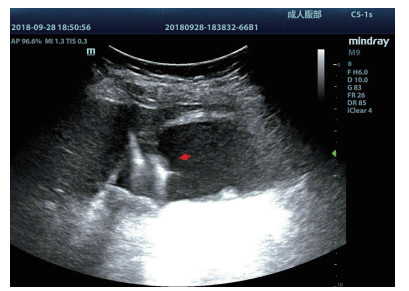

术前经肘静脉超声造影:行PTGBD前半h经肘静脉快速团注SonoVuel 5 mL,在对比脉冲序列造影成像模式下进行观察,根据不同组织造影剂凝聚的时间及浓度差异,判断胆囊周围组织黏连程度、胆囊壁完整程度(图 1),如出现胆囊壁造影剂充盈缺损(图 23),则考虑胆囊壁坏死或穿孔,根据静脉造影情况选择合适的置管入路,避开胆囊穿孔的部位及黏连组织。

图 1 经肘静脉超声造影胆囊图像,造影图(左),二维超声图(右)